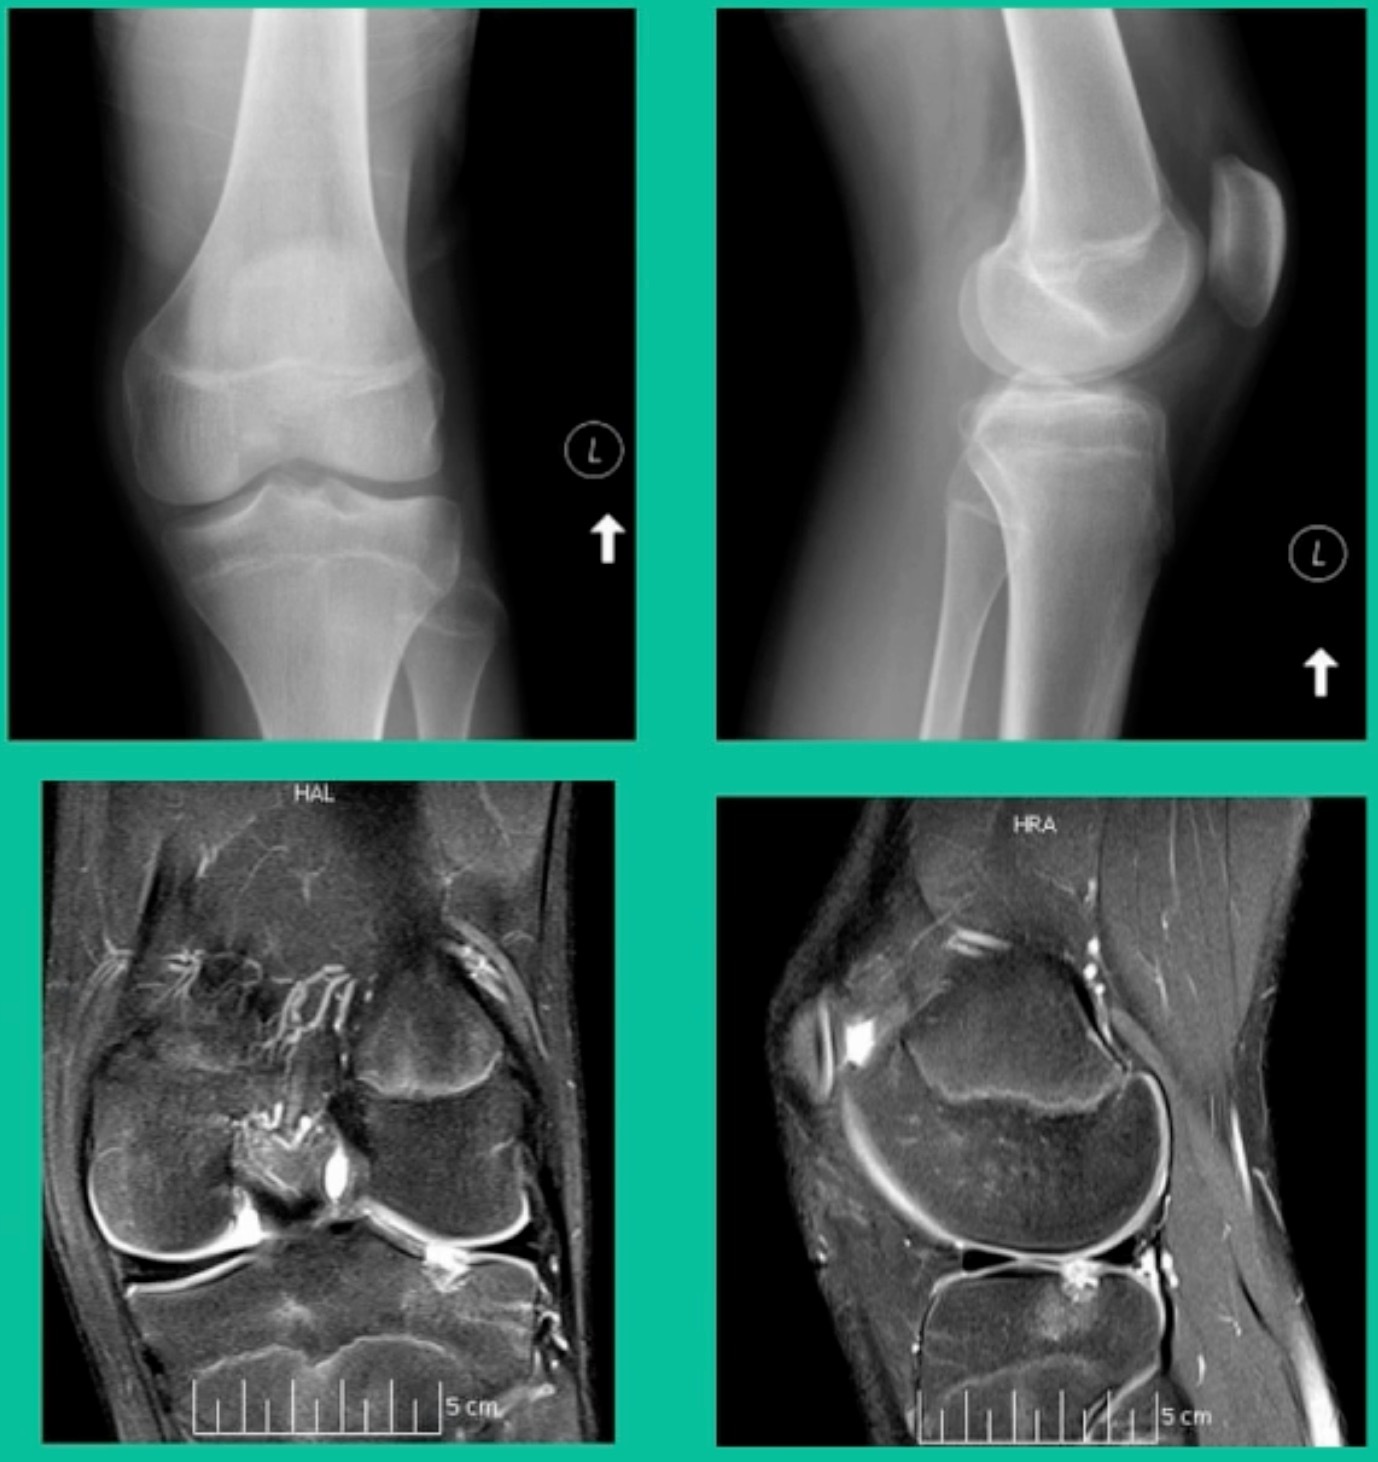

43-Year-Old, symptomatic medial femoral condyle.

D1 football player formally, affecting ADLs. For this one, I initially just wanted to watch it. This looks pretty small when he came in. Let’s see what happens. Six months later, this is where he progressed to.

We get in there, it’s delaminated, not much bone, nothing to fix in my mind, and so we drilled it.

How do these do? There’s actually reasonable data for marrow stimulation for OCD. But if you have the option for small defects, I would prefer an osteochondral allograft over microfracture based on the literature. That’s the take-home. Marrow stimulation, if you do it, you’re probably better off drilling it. We showed that we could reduce revision rates with marrow stimulation by two-thirds if you drill it versus use a microfracture awl.